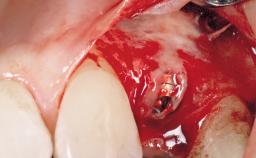

Immediate Placement of an Implant in a Maxillary Left Central Incisor Site

Placement Protocol Immediate implant placement

Socket Morphology Single-root socket

Socket Integrity Damage to one or more bone walls

Bone Volume Damage to one or more socket walls